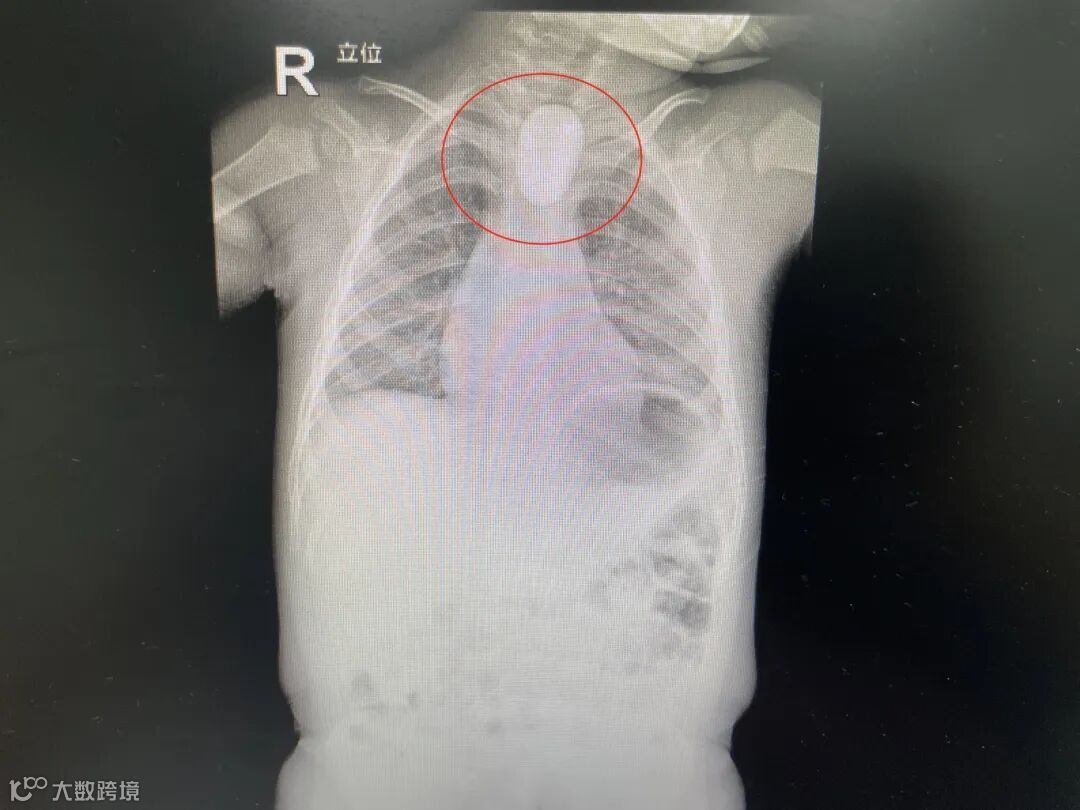

据家长反映,5月4日下午,孩子在小区内玩耍,捡了水池边的一块鹅卵石拿回了家。过了不久,家长发现孩子手中的鹅卵石不见了,找遍了家里都没有找到,怀疑是不是孩子给吞进了肚子。于是来到医院就诊,经过拍片检查发现,孩子的食道口确实存在着一块椭圆形的东西。